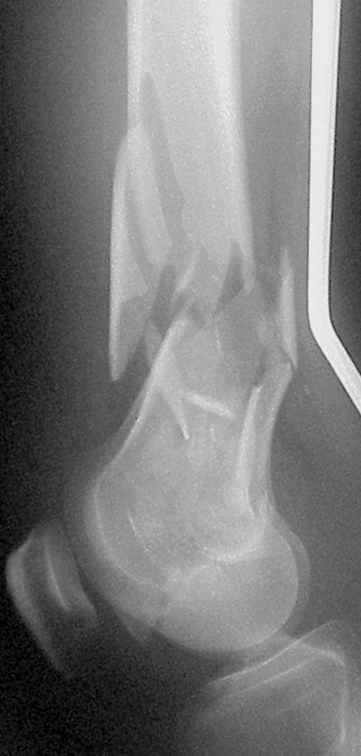

This 40 yo male suffered a car accident on Monday. His lesiones were:

- Left tibia fracture (41-A3.3) closed

- Right femur fracture (33-C3.3) open grade III-A

On Wednesday we operated him, we used a LISS plate in either bone, when drillind we had the feeling of a 'normal' bone.

On Thersday afternoon he was alright, he is a very active man and he was moving well both knees. Later that evening he told me that while he was a little bit asleep he turned on the bed and felt pain and that the femur was loose. Here are the X-rays we took.